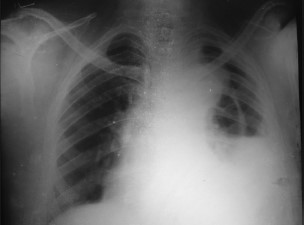

Colega quer transferir às 3 horas da manhã, do hospital de Viamão, paciente com 72 anos atendido na Emergência, apresentando dor retroesternal há duas horas. Relata que o paciente está com PA 110/70mmHg e sudorético. A ausculta cardíaca na fúrcula esternal (Fig. A), o Rx de tórax (Fig. B) e o eletrocardiograma (Fig. C), transmitidos via eletrônica, estão representados abaixo.

Fig. A

Fig. B

Fig. C

Com relação ao caso acima, se você estivesse em centro de referência, qual seria a melhor conduta?